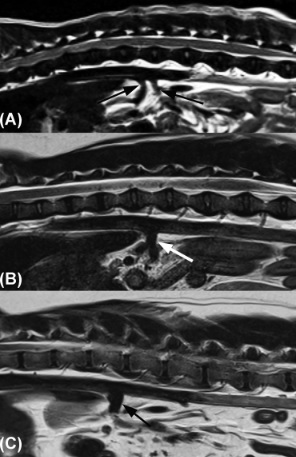

Lee et al 2022; 3.0-Tesla MRI of normal canine adrenal glands: Which sequence allowed the best visualization of the adrenal glands? What sequence allowed visualization of corticomedullary definition?

1) 2D TSE

2) T2W imaging. The medulla is T2 hyperintense.